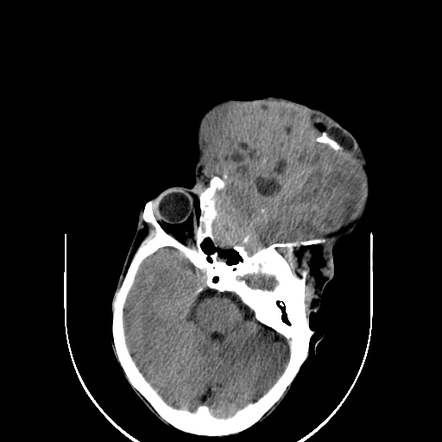

Rhabdomyosarcoma (orbit) | Radiology Reference Article | Radiopaedia.org

radiopaedia.org

radiopaedia.org

rhabdomyosarcoma orbit orbital hemangioma radiopaedia radiology imaging

Rhabdomyosarcoma (orbit) | Radiology Reference Article | Radiopaedia.org

radiopaedia.org

radiopaedia.org

rhabdomyosarcoma orbit radiology radiopaedia